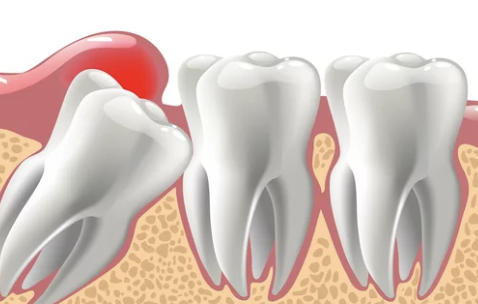

- 부분 매복 상태에서는 잇몸 주위에 음식물 찌꺼기가 쉽게 쌓여 염증(치주염)이 생기기 쉽습니다.

- 염증이 심해지면 농양이나 심각한 잇몸 감염으로 이어질 수 있습니다.